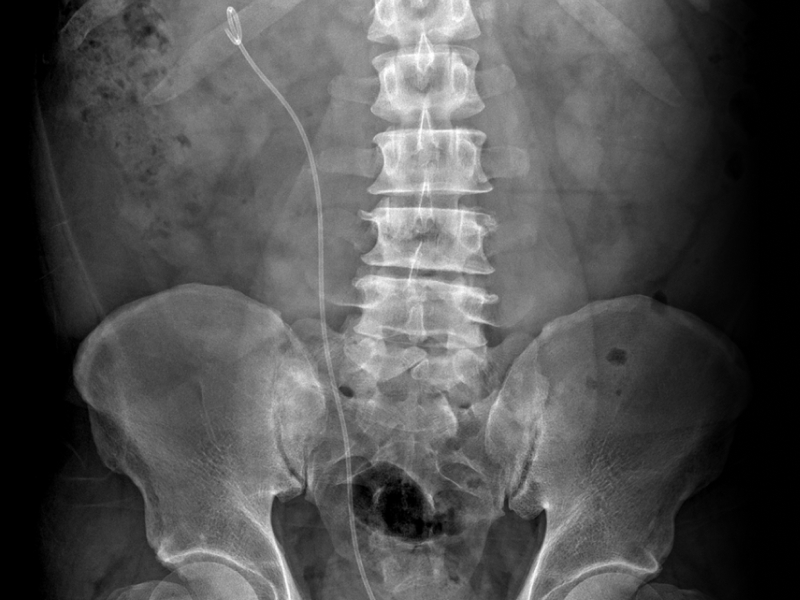

It’s Advanced! 요관내시경 결석 제거술,

쇄석술로 제거되지 않는 결석, 재발이 잦은 결석, 위치가 나쁜 결석 등 여러 요인을 고려해 가장 효과적인 수술을 제공합니다.

보통 1~2일 내 퇴원하며 가벼운 활동은 빠르게 가능합니다. 스텐트는 며칠 후 제거합니다.

요관 손상, 출혈, 감염, 잔석 등의 부작용이 드물게 발생할 수 있으나 대부분 경미하고 일시적이며 적절한 조치로 회복이 잘 됩니다.

수술 후 하루 이내 가벼운 활동은 대부분 가능합니다. 무거운 물건 들기나 격한 운동은 1~2주간 피하는 것이 좋습니다. 스텐트가 있다면 제거 후 더욱 편하게 생활할 수 있습니다.

하루 2리터 이상 물을 마셔 소변량을 충분히 유지하는 것이 중요합니다. 식단 조절, 결석 성분 분석, 정기 검진도 큰 도움이 됩니다. 재발률이 높은 질환이므로 꾸준한 관리가 필요합니다.

수술 후 요관 부종이나 폐쇄를 방지하기 위해 대부분 삽입합니다. 이는 불편감은 있을 수 있지만 요관 회복에 중요한 역할을 하며 보통 1~2주 후 외래에서 간단히 제거합니다.